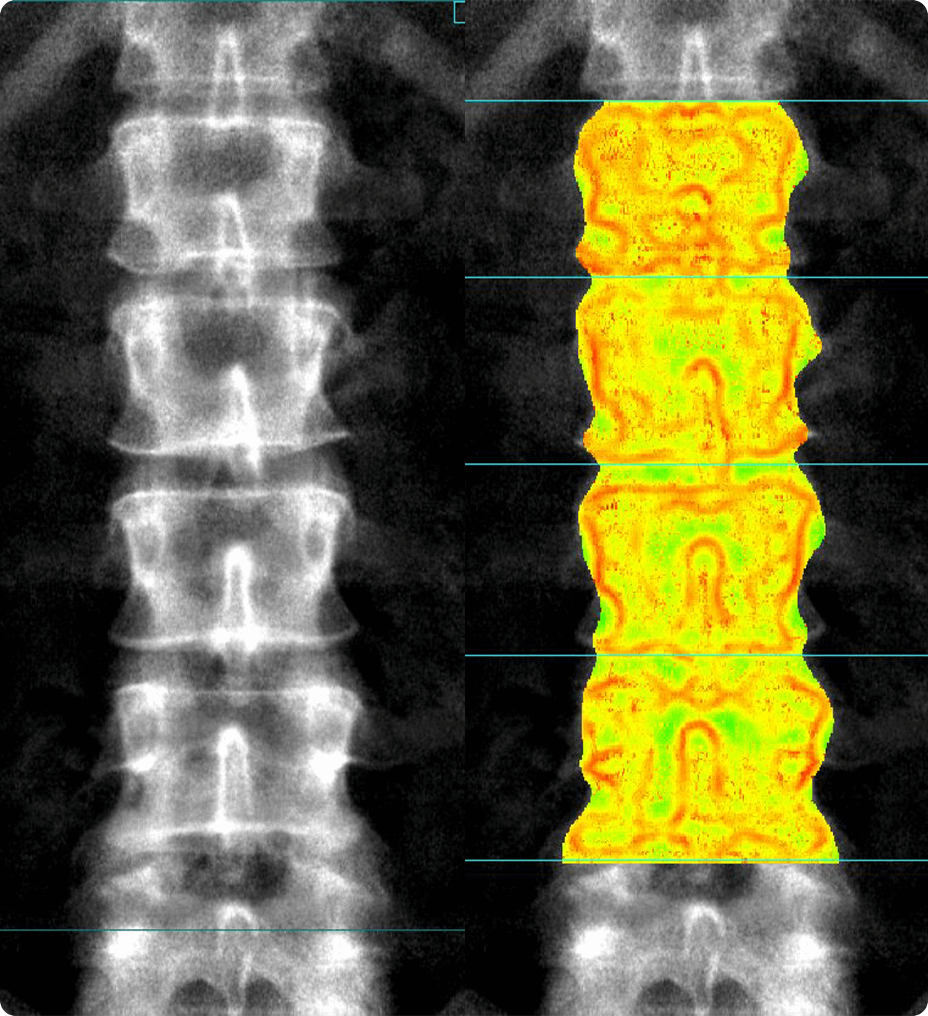

Améliorez votre qualité d’image IRM avec la technologie de reconstruction AIR™ Recon DL

Une meilleure imagerie, tout simplement